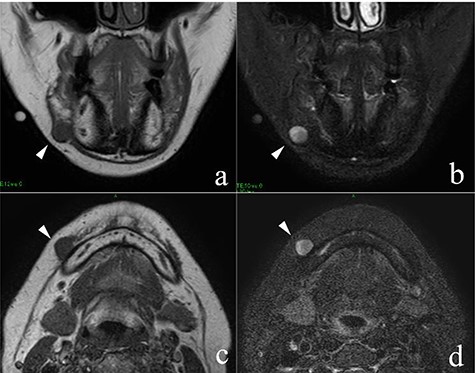

She had a 15-mm, painless, non-pitting and indurated mass at the right mandibular margin (Fig. 1). Oral examination revealed no mucosal abnormalities or swelling. The mass was difficult to palpate from the oral side due to the presence of buccal frenulum on the mucosa over the mass. Magnetic resonance imaging (MRI) revealed a 15-mm nodule with a clear border at the right mandibular margin, with low and high signal intensities on T1- and T2-weighted images, respectively (Fig. 2). Computed tomography (CT) revealed a 15-mm low-density nodule in the right mandibular margin. Calcification, bone invasion or lymph node enlargement were not observed (Fig. 3). The mass was radiologically diagnosed as an epidermoid cyst. The differential diagnoses were schwannoma, neurofibromatosis, pleomorphic adenoma and a powdery mass; however, schwannoma was considered to be most likely.

MRI findings; the arrowheads indicate the schwannoma; (a) low signal intensity on T1-weighted coronal image; (b) high signal intensity on T2-weighted coronal image; (c) low signal intensity on T1-weighted axial image; (d) high signal intensity on T2-weighted axial image.